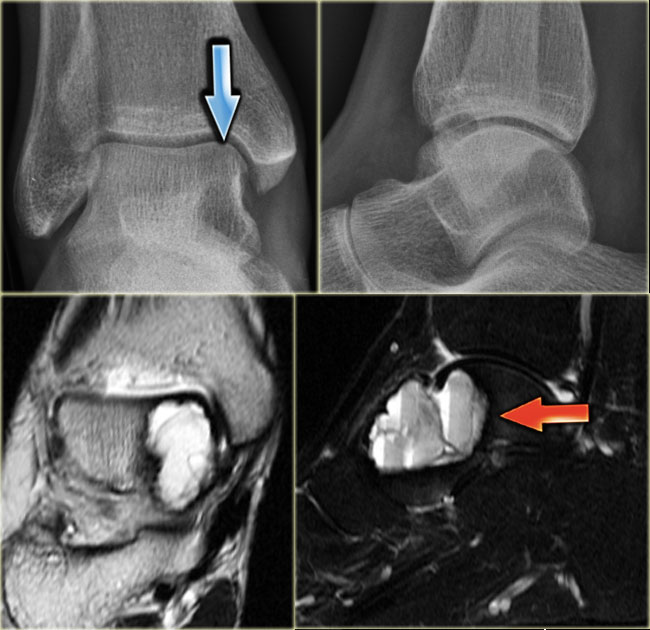

ABC (5)

On the left an expansile well-defined osteolytic lesion with a sclerotic margin in the talus.

Axial PD-weighted image shows lobulated contours and cystic appearance with fluid-fluid level (arrow).

Most likely diagnosis: ABC.

Differential diagnosis:

chondroblastoma with secondary ABC.